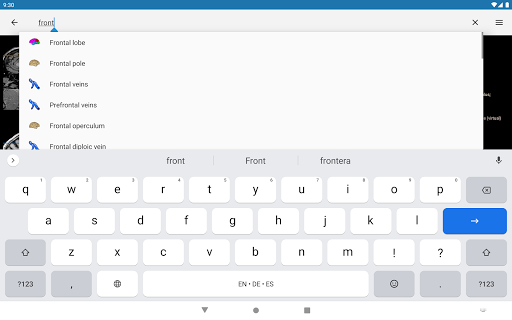

*Improving performance of anatomical structure search

*Find your anatomical parts more easily thanks to the new, more intuitive and powerful search feature